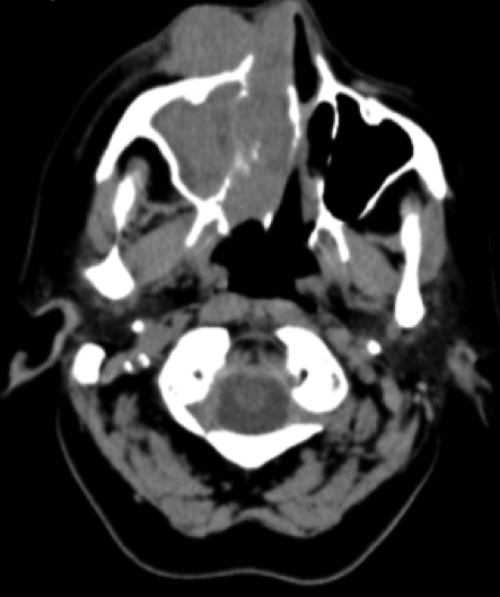

Figure 1: CT of lesion: transverse and coronal views.

The patient was further investigated with CT head and orbits. The scan showed an intraorbital soft tissue mass with extension into the right maxillary, sphenoid and ethmoidal sinuses and into the medial orbit (Figure 1). A biopsy of the right nasal mass was taken and reported as large cell non-Hodgkin’s lymphoma on histopathology examination. The patient underwent CHOP chemotherapy (cyclophosphamide, doxorubicin, vincristine, prednisone) followed by local radiotherapy.